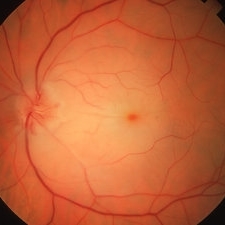

Embolic Central Retinal Artery Occlusion

58-year-old WM with embolic CRAO demonstrating a a cherry-red spot in macula, retinal whitening around the fovea, and the embolus in a inferotemporal branch retinal arteriole; VA= HM 6''

Imaging device: Topcon VT-50

Condition/keywords: central retinal artery occlusion (CRAO), cherry red spot, embolus, retinal whitening